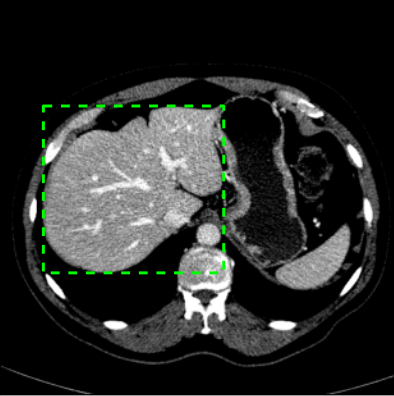

Box prompt

Boxes have been reported to be the most effective prompts in SAM framework [16, 17]. Compared to points, boxes inherently provide more comprehensive information. Nevertheless, it is imperative to acknowledge that the utilization of boxes presents inherent challenges, particularly in the segmentation of non-convex objects. Additionally, boxes are notably susceptible to the box jitter [17]. Consequently, during the phase of box prompt-learning, random box jitter in range of has been intentionally introduced into the training stage. The introduction of box jitter aims to facilitate the training of a more robust box embedding, capable of accommodating across diverse annotation deviations. A simple illustration of the box jittering is shown in Fig. 6.

In the validation stage, the box jitter has also been implemented during the inference to replicate the users’ actual annotation processes, which might deviate from the ground truth.